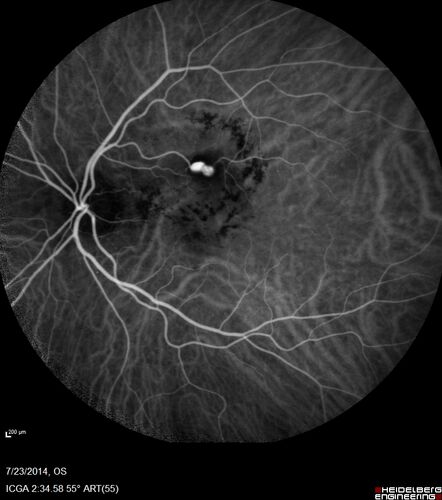

89 year old female with peripapillary CNVM treated with Lucentis. Vision was 20/25 OS 3 weeks ago.  She noticed vision loss OS.  Vision had dropped to 20/60.  She had a fresh MA and was treated with laser.

Retinal Arterial Macroaneurysm treated with Laser